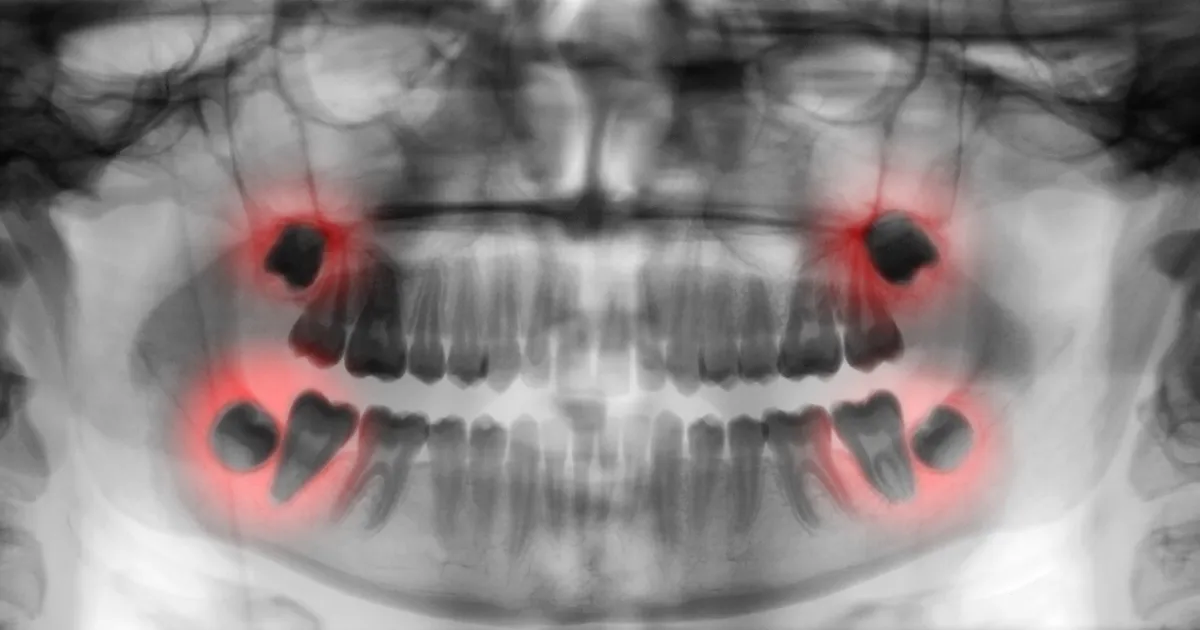

親知らず抜歯で腫れやすい理由

親知らずの抜歯後に腫れが生じるのは、次のような理由があります。

- 抜けるまでに時間がかかる(難抜歯)

- 顎の骨の一部を削る処置を伴う抜歯の場合

- 歯ぐきの切開を伴う抜歯の場合

親知らずが深く埋まっている場合や、抜歯に時間がかかると、周囲の組織がダメージを受けるため、腫れやすくなります。

顎の骨の一部を削る処置を伴う抜歯の場合

親知らずが顎の骨に埋まっている場合、骨を一部削る処置が必要になります。これによって腫れが強くなることがあります。

歯ぐきの切開を伴う抜歯の場合

親知らずを抜く際、歯ぐきを切開することが必要なケースがあります。この場合も腫れがひどくなる可能性がありますが、通常数日から1週間程度で改善します。